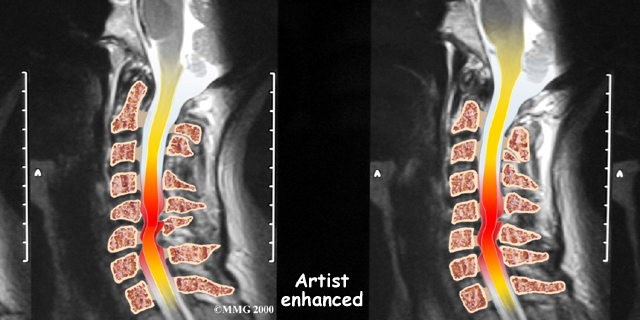

If more information is needed, a magnetic resonance imaging (MRI) scan may be ordered. The MRI machine uses magnetic waves rather than X-rays to show the soft tissues of the body. This test gives a clear picture of the spinal cord and can show where it is being squeezed. An MRI machine creates pictures that look like slices of the area your healthcare professional is interested in. This test does not require any special dye or a needle.

Degeneration is the most common cause of spinal stenosis. Wear and tear on the spine from normal aging and from repeated stress and strain can cause many problems in the cervical spine. The intervertebral disc can begin to collapse, shrinking the space between the vertebrae. Bone spurs (small bony projections) may form that protrude into the spinal canal and reduce the space available for the spinal cord. The ligaments that hold the vertebrae together may become thicker and can also push into the spinal canal. All of these conditions narrow the spinal canal.